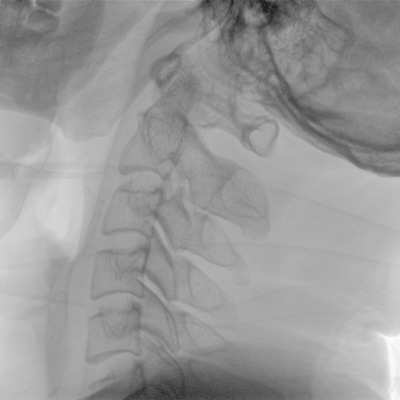

骨科: 經(jīng)皮錐體成形術(shù)、經(jīng)皮椎間盤臭氧治療術(shù)、胸脊椎固定、骨活檢、腰椎內(nèi)固定術(shù)等。